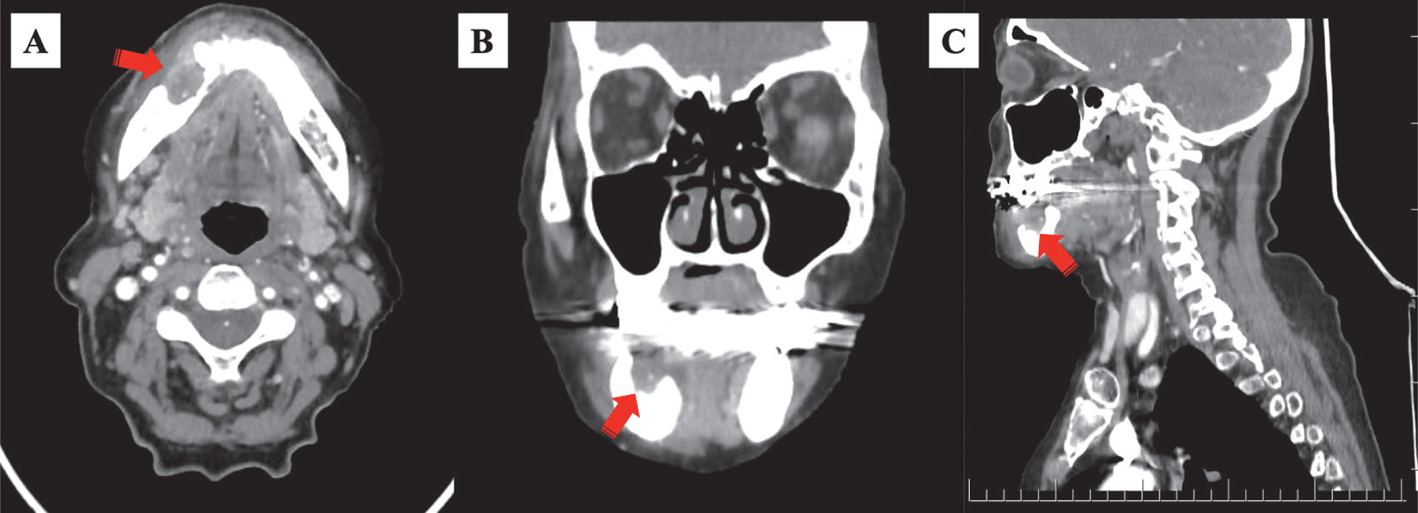

Computed tomography (CT)

The typical CT findings of ORNJ include bone sequestrum, pathological fractures, osteolysis, changes in the trabecular structure, thickening of soft tissues, and cortical discontinuity (19, 39) (Figure 3). The loss of bone trabeculae in the cancellous bone with bicortical involvement on a CT scan in the later stages of ORNJ is one of the distinctive features of the disease. Gas bubble-like lesions can be seen on CT scans, which may be indicative of an infectious process that is pathognomonic for osteomyelitis (37, 87). Any abnormal growth in the surrounding soft tissue should be considered a second primary cancer or a tumor recurrence to rule out the possibility of either (37). ORNJ can be distinguished from these conditions when permeating trabeculation and bone sclerosis are visible on a CT scan (88). The diagnosis of ORNJ is improved by localized cortical defects that are located far from the primary tumor (89).

Fig 3

Figure 3. Computed tomography. Osteoradionecrosis in the anterior of the right mandible corpus is demonstrated as a lytic, slightly expansile, and defective region (red arrows). A: axial; B: coronal; C: sagittal.

The buccal, lingual, or both sides of the jaw may have cortical discontinuities associated with ORNJ. The presence of discontinuities in both the lingual and corresponding buccal cortex is widely recognized as an indication of a jaw fracture (85). Because CT is 3D rather than 2D, bone changes in the anterior-posterior direction and involvement of the buccal or lingual cortex are more visible. Furthermore, OPT cannot discriminate between lingual and buccal bone degeneration, which is easily seen by CT (89, 90). The pathology is confined to the bone in the absence of a pathological fracture, but the presence of a nearby fusiform swelling reveals soft tissue thickening and involvement around the pathological fracture, if one exists (85). In the absence of soft tissue involvement, mandibular bone deterioration aids in ORNJ diagnosis (91). It may be difficult to distinguish advanced ORNJ from tumor recurrence because it frequently coexists soft tissue edema. To assist in the diagnosis, it might be beneficial to be aware that a malignant squamous cell carcinoma frequently results in damage to the alveolar process or the lingual cortex (85). Additionally, ORNJ varies from tumor recurrence in that the median ORNJ development gap following RT or CCRT is approximately three years, whereas tumor recurrences often occur during the first two years of treatment (92).